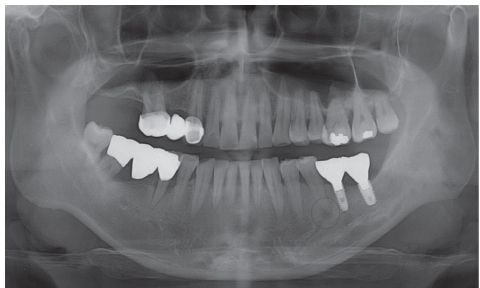

Figure 11

One year before implant surgery: Note that the posterior area of mandibular left segment was edentulous.

Figure 11 One year before implant surgery: Note that the posterior area of mandibular left segment was edentulous.